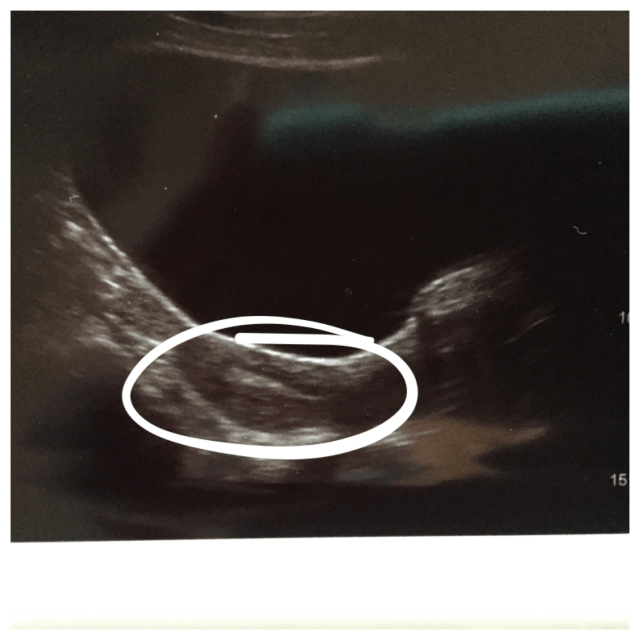

And here they go:

You can see two little white dots – that’s the air pockets pushing the embies into their new home! All around it is my lining where they’ll implant in the next 24-36 hours! I hope they find a ‘Home Sweet Home’ sign soon!!